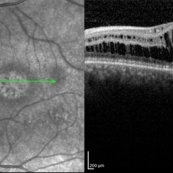

Central Areolar Choroidal Dystrophy Central Areolar Choroidal DystrophyJul 7 2015 by Hamid Ahmadieh, MD OCT images of both eyes of a 58-year-old man with progressive loss of vision. VA OD is 20/60 and VA OS is 20/400. Photographer: Soulmaz Shahmohammad, Negah Eye Center, Tehran, Iran Imaging device: Specteralis Condition/keywords: central areolar choroidal dystrophy (CACD), optical coherence tomography (OCT)